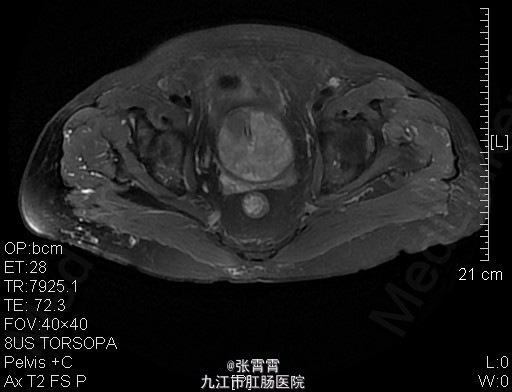

6、诊断:前列腺增生,膀胱结石,高血压 7、处理:住院后完善相关检查,盆腔MR平扫+增强扫描:1、前列腺增生并癌变,考虑侵犯前列腺包膜。2、慢性膀胱炎。3、双侧腹股沟区多发稍大淋巴结,考虑前列腺癌(早期)。诊断为前列腺增生。目前已排除手术禁忌证。予术前检查后行经尿道前列腺剜切术+耻骨上膀胱造瘘术+切开取石术,手术顺利,术后组织病理检查示前列腺增生,术后恢复顺利。